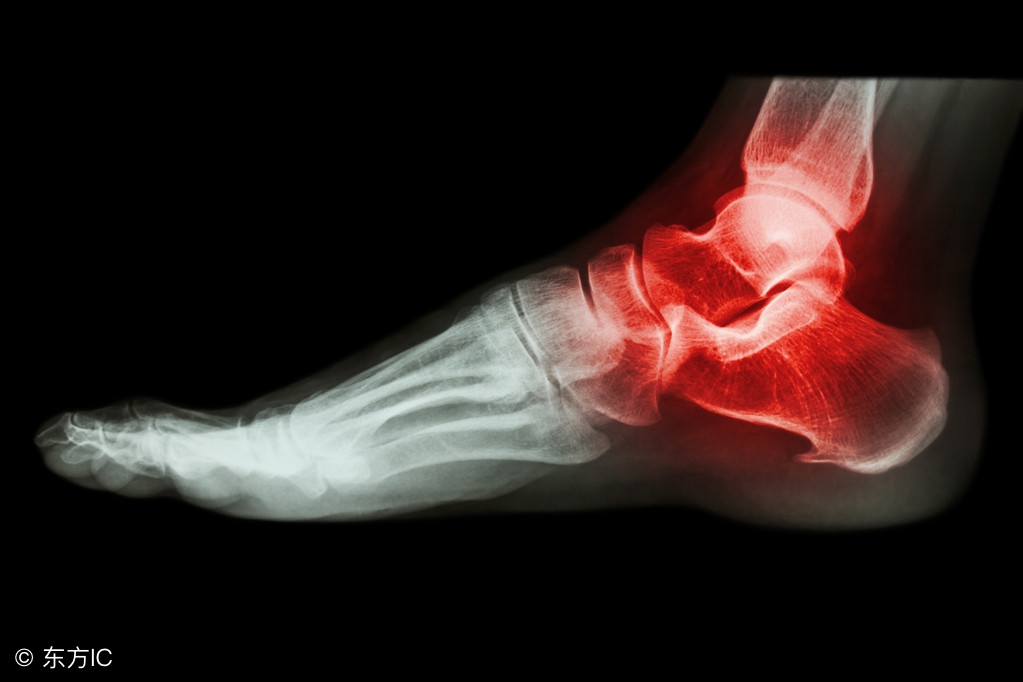

在季前赛中扭伤了右脚踝,

今日更新的X光检查结果显示为阴性

(无结构性损伤)

踝关节扭伤是运动损伤中发生率最高的,发生的原因大多是身体失去重心,落地时踩在别人的脚上或脚被绊倒时出现。扭伤时,局部会发生关节肿胀、疼痛,严重时甚至造成骨折。